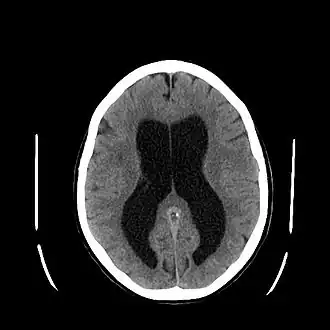

![]() Tomografía computada mostrando acumulación del líquido cefalorraquídeo: zona hipodensa (oscura). | ||

La acumulación excesiva de líquido cefalorraquídeo tiene como consecuencia una dilatación anormal de los espacios en el cerebro llamados ventrículos. Esta dilatación ocasiona una presión potencialmente perjudicial en los tejidos del cerebro, generalmente el aumento del líquido en los ventrículos cerebrales es producido por la obstrucción de los conductos situados por debajo del cerebelo.